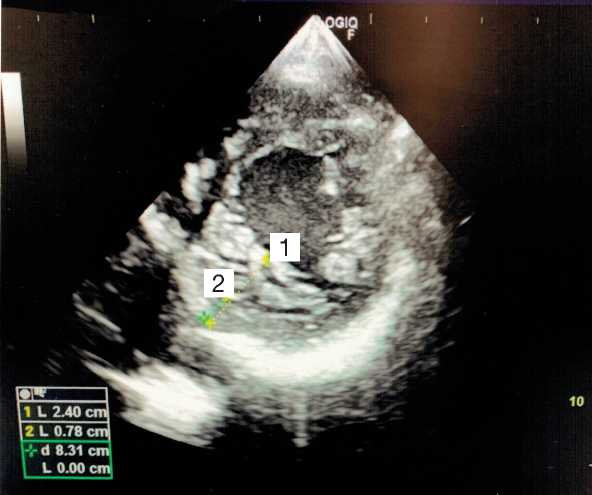

ЭхоКГ при поступлении: фракция выброса левого желудочка 35%; повышенная трабекулярность миокарда левого желудочка (рис. 3).

Рис. 3. Измерение некомпактного и компактного слоя миокарда левого желудочка в парастернальной позиции по короткой оси на уровне папиллярных мышц в конце диастолы: 1 — размер-некомпактный слой + компактный слой; 2 — размер-компактный слой.